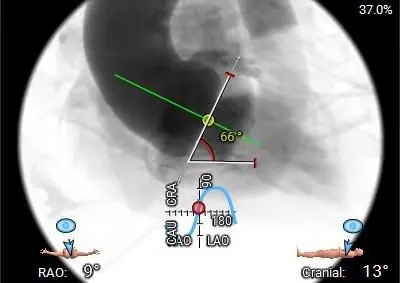

66°横位心

-

右侧股动脉主入路,超硬导丝支撑下植入大鞘,左侧辅入路

冠脉风险不高,不进行提前保护,球囊预扩及瓣膜释放过程中评估冠脉灌注情况

建议20mm球囊预扩,患者小心室,小球囊扩张降低循环崩溃风险

使用ScienCrown™全可回收主动脉瓣膜系统植入TF27号瓣膜

手术操作:该患者重度钙化,释放过程中需警惕瓣膜下滑风险,瓣膜释放后需评估瓣膜展开情况及瓣周反流情况。其次该患者为横位心,术中避免提拉输送系统,保证瓣膜同轴性,充分利用全可回收功能,评估瓣膜位置。

初始造影确定瓣环位置

20mm球囊预扩,无腰有漏;选择27号瓣膜可充分封堵

瓣膜0位定位释放,导丝保持张力,保证同轴性

瓣膜展开后造影评估瓣膜位于0位,无瓣周漏

多角度评估,瓣膜位置可,同轴性佳,可以脱钩释放

脱钩后造影,瓣膜无位移,无瓣周漏